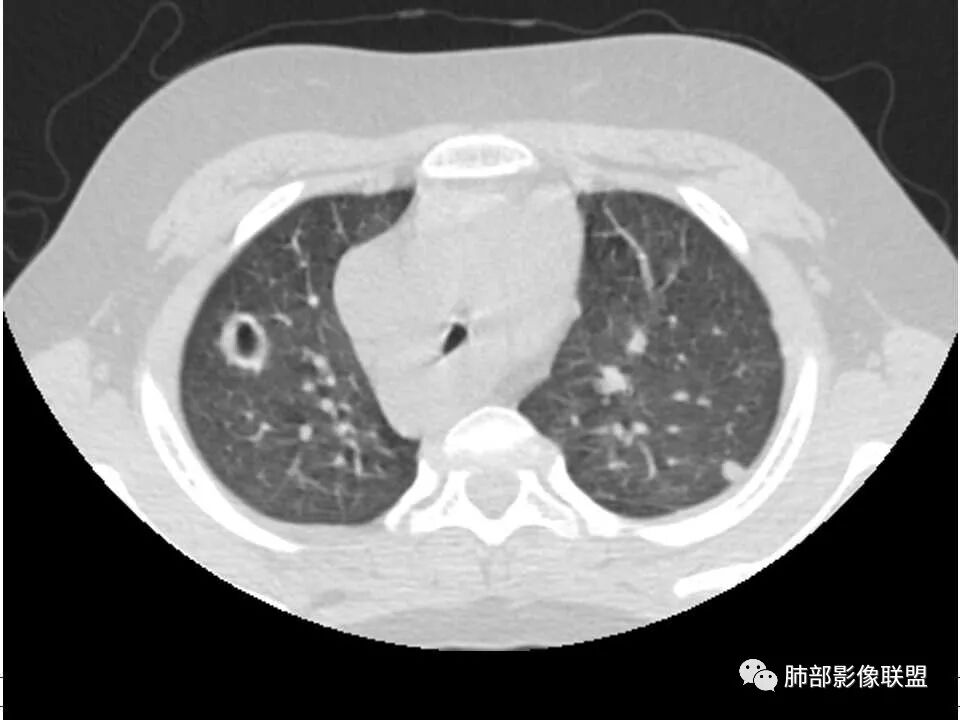

晨读,儿童,起病急,病程短,有下肢疼痛伴肿胀病史,发热,白细胞升高,结合下肢辅查,考虑骨髓炎,胸部ct:双肺多发空洞,结节,外带下叶为主,空洞内外光滑,无丝状物,有血管滋养征,综合病史及影像考虑脓毒性肺栓塞,金葡可能性大,建议痰培养,血培养,必要时ngs。

双肺多发结节,空洞,与胸膜相连,血道来源,空洞内壁光滑,结节周围模糊,考虑金葡菌感染。

有脓毒性肺栓塞了,有空洞,有结节,有血管滋养征,考虑血源性金葡菌感染

小儿,急性起病,下肢疼痛,mr提示骨髓水肿,临床化验炎性指标高,考虑金葡菌骨髓炎,双肺多发结节,以血管支气管束及胸膜下分布为主,部分结节近端与血管相连,部分结节可见空腔,内壁光整,部分囊腔有张力,考虑骨髓炎并肺内血播感染,金葡?

1. 多发胸膜下外周结节、< 3 cm 的楔形影和滋养血管征 CT 表现;

4.经恰当的抗生素治疗,肺部浸润影吸收。滋养血管征为一支血管影连接肺部周边病灶,在 2/3 以上患者出现,可作为高度提示 SPE 的征象。